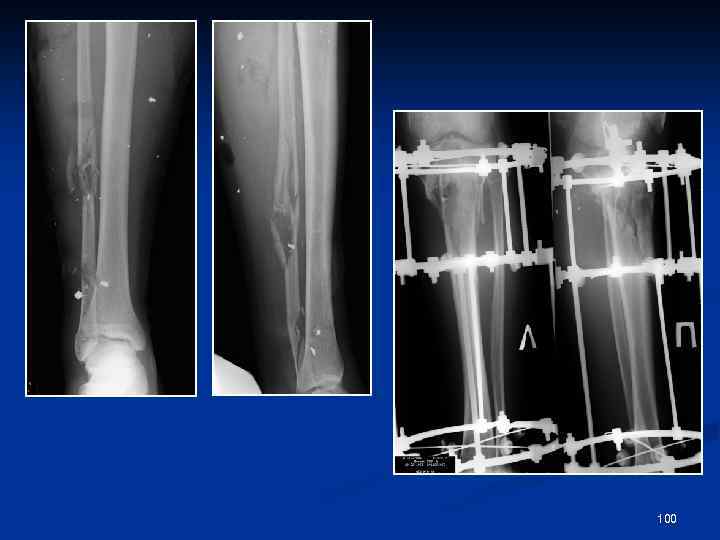

Огнестрельная травма голени 80

99

100